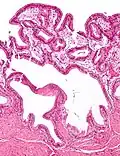

| Micrografia da colesterolose da vesícula biliar. Mancha de H&E. | |

Na patologia cirúrgica, vesícula biliar de morango, mais formalmente colesterolose da vesícula biliar e colesterolose de vesícula biliar, é uma alteração na parede da vesícula biliar devido ao excesso de colesterol.[1]

O nome vesícula biliar de morango vem da aparência tipicamente pontilhada da superfície da mucosa, em um exame grosseiro, que se assemelha à aparência de um morango.

Colesterolose da vesícula biliar (Imagem grosseira). Micrografia da colesterolose da vesícula biliar.

Micrografia da colesterolose da vesícula biliar. Micrografia da colesterolose da vesícula biliar.

Micrografia da colesterolose da vesícula biliar. Micrografia da colesterolose da vesícula biliar.

Micrografia da colesterolose da vesícula biliar.